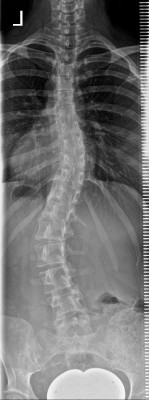

Mein tragbares CCtec-Korsett hatte links recht hoch gedrückt, bei T11/T12, da ist kaum noch die oberste Spitze des Lendenwulstes, trotzdem ging er zurück. In den Röntgenbildern sehe ich aber tatsächlich kaum einen Unterschied. Vielleicht sind die etwas ungenau? Aber ich muss gestehen, ich bin verwirrt. Ich versuche mal, euch die Bilder anzuhängen.

- Dateianhänge

-

- Vor Korsettbehandlung

- 2008-01-23.jpeg (17.96 KiB) 22322 mal betrachtet

- Im letzten Rahmouni-Korsett

- 2013-11-29.jpeg (23.61 KiB) 22322 mal betrachtet

- Eine Woche ohne Korsett nach 7 Jahren Rahmouni-Korsett

- 2015-02-04.jpeg (20.64 KiB) 22322 mal betrachtet

- 6 Monate ohne Korsett nach 7 Jahren Rahmouni- und einem Jahr CCtec-Korsett

- 2017-01-05.jpeg (17.17 KiB) 22322 mal betrachtet

ich finde es auch recht schwer zu erkennen, weil die Röntgenbilder wohl von unterschiedlicher Qualität sind (sieht zumindest für mich so aus). Tut mir leid, wenn ich zu Deiner Verwirrung beigetragen habe